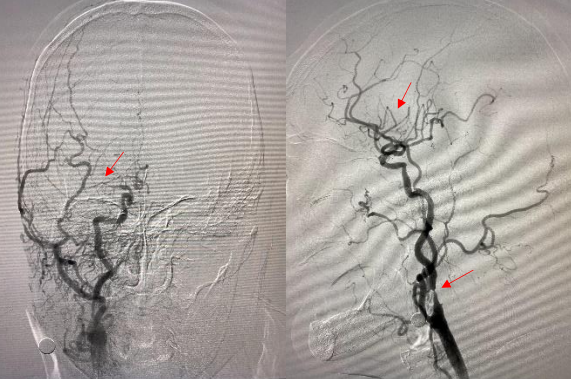

遂果断另辟蹊径,经肱动脉穿刺成功,行腹主动脉造影证实右侧髂总动脉闭塞,左侧髂总动脉极重度狭窄并串珠样改变,故经股动脉入路此路不通。

头颈部血管造影提示:患者为右侧颈内动脉极重度狭窄合并右侧大脑中动脉闭塞。

由远及近,优先开通右侧大脑中动脉恢复颅内血流,再行右侧颈内动脉起始部支架植入血管成形,顺利开通闭塞血管,颅内血流恢复。